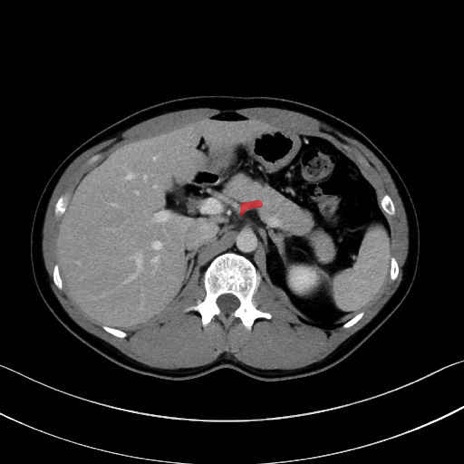

【症例】20歳代 男性 スクリーニング

■起始:典型的には腹腔動脈幹(celiac trunk)から左胃動脈・総肝動脈とともに三分岐し、脾動脈は左後上方へ向かう。

■走行:膵上縁または膵実質背側を蛇行しながら左方へ進み、膵尾部近傍で脾門へ至る。蛇行の程度は個体差が大きい。

■終枝:脾門部で複数の終末枝に分かれ、上極・下極枝や脾門枝群を形成する。胃短動脈群や左胃大網動脈はしばしば脾動脈から分岐する。